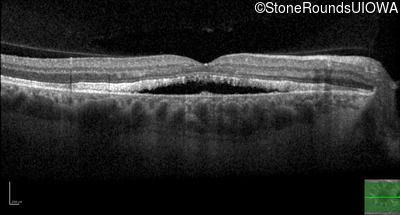

Best Disease (IIB)

Age at visit: 49 years

This 49 year old man first experienced some mild metamorphopsia at age 35.